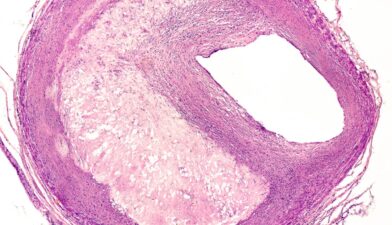

Sepesialis Bedah